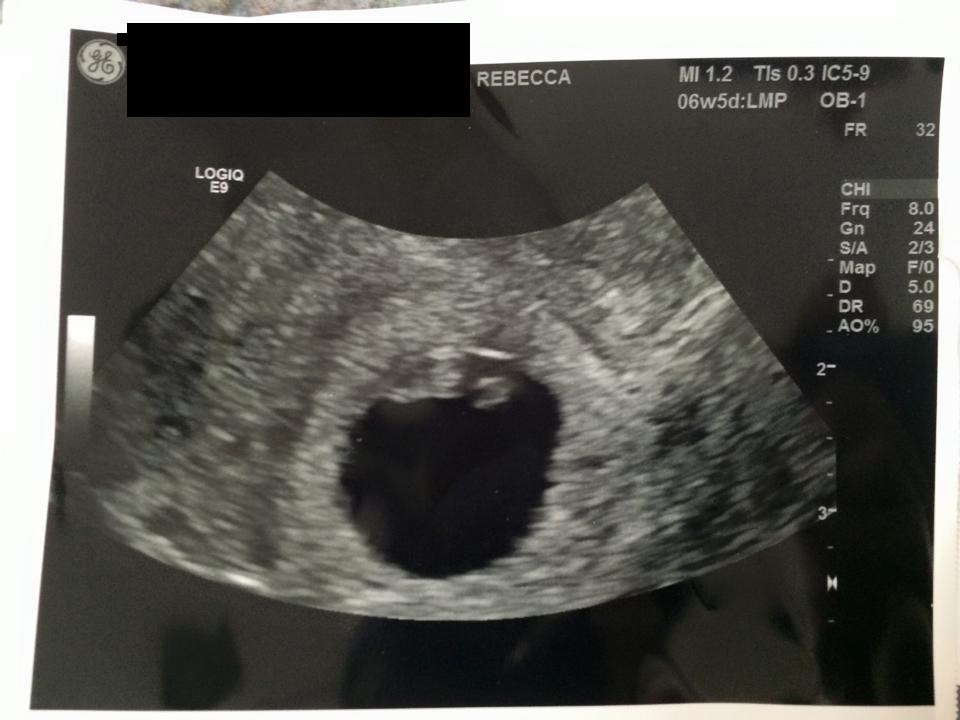

Attachment 27630